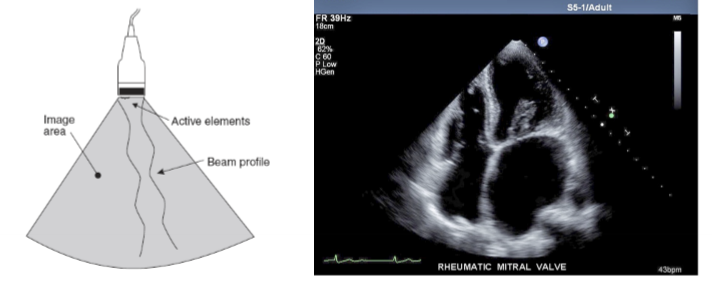

sector array

all elements are fired simultaneously

beam is electronically focused and steered

used in cardiac and brain imaging